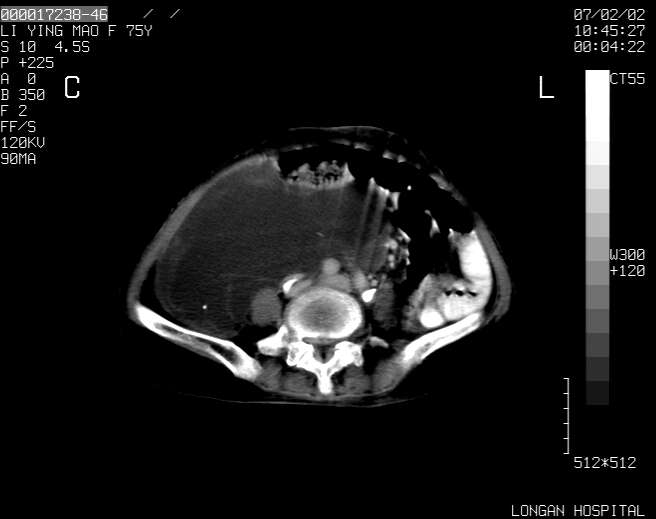

以下是引用dyqct在2007-2-10 8:53:00的发言:[br]考虑:1、肝脏多发囊肿[br] 2、左肾囊肿,右肾多发结石并积水。[br] 3、右胸少量积液。[br] 4、右肾周包裹性积液或淋巴管瘤(有见缝就钻的征象、薄隔、小结节状钙化)?[br] 5、腰椎动脉瘤样骨囊肿?[br] [br] [br]